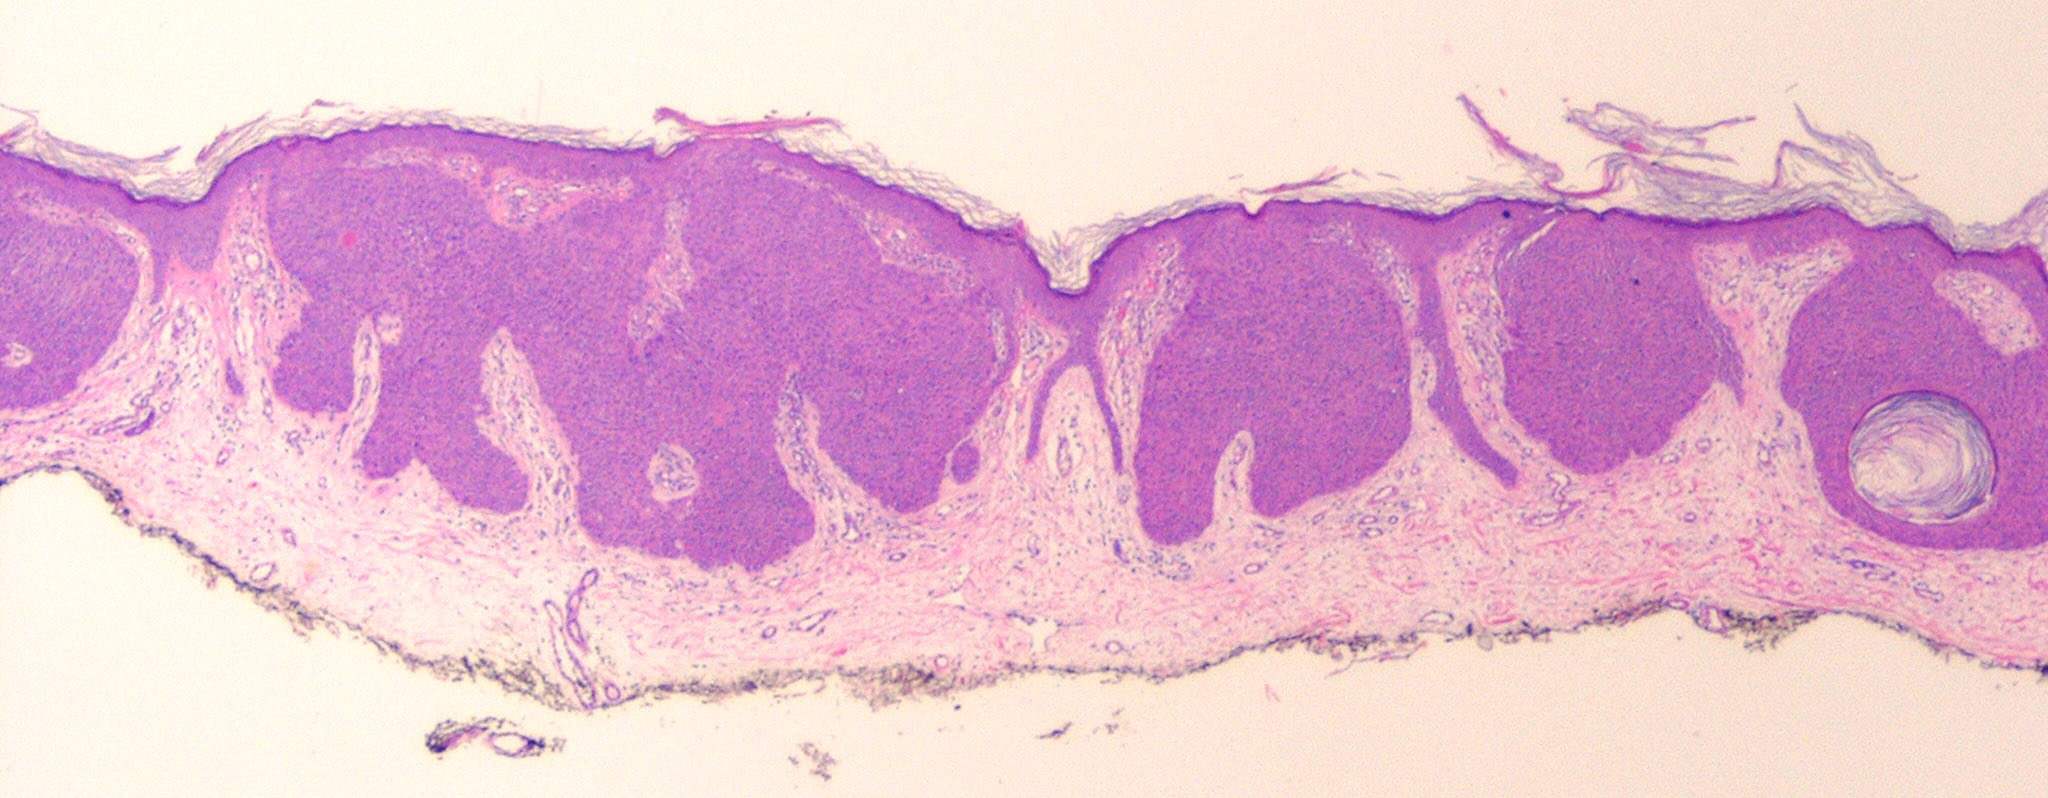

Hidroacanthoma_simplex = الشوكوم العرقي البسيط

OLYMPUS DIGITAL CAMERA